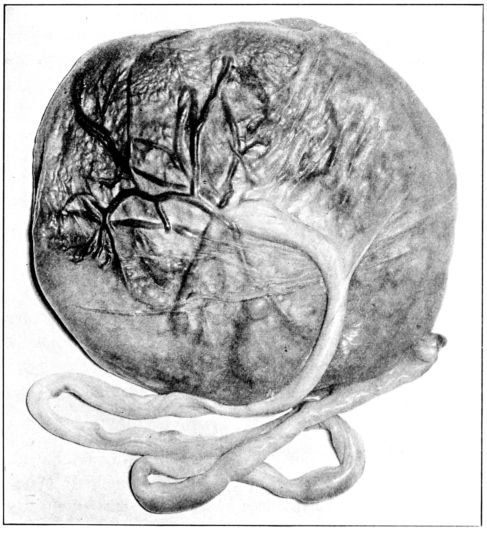

| 24. | Fetal surface of the placenta | 75 |